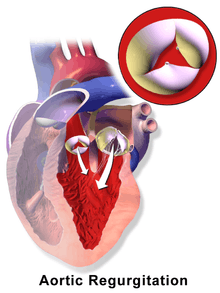

Aortic insufficiency (AI), also known as aortic regurgitation (AR), is the leaking of the aortic valve of the heart that causes blood to flow in the reverse direction during ventricular diastole, from the aorta into the left ventricle. As a consequence the cardiac muscle is forced to work harder than normal.[1]

The mechanism of aortic insufficiency (AI), comprises the pressure in the left ventricle falling below the pressure in the aorta, the aortic valve is not able to completely close. This causes a leaking of blood from the aorta into the left ventricle. This means that some of the blood that was already ejected from the heart is regurgitating back into the heart. The percentage of blood that regurgitates back through the aortic valve due to AI is known as the regurgitant fraction. This regurgitant flow causes a decrease in the diastolic blood pressure in the aorta, and therefore an increase in the pulse pressure. Since some of the blood that is ejected during systole regurgitates back into the left ventricle during diastole, there is decreased effective forward flow in AI.[6][7]

Physiology in individuals with a normally functioning aortic valve, the valve is only open when the pressure in the left ventricle is higher than the pressure in the aorta. This allows the blood to be ejected from the left ventricle into the aorta during ventricular systole. The amount of blood that is ejected by the heart is known as the stroke volume. Under normal conditions, >50% of the blood in a filled left ventricle is ejected into the aorta to be used by the body. After ventricular systole, the pressure in the left ventricle decreases as it relaxes and begins to fill up with blood from the left atrium. This relaxation of the left ventricle (early ventricular diastole) causes a fall in its pressure. When the pressure in the left ventricle falls below the pressure in the aorta, the aortic valve will close, preventing blood in the aorta from going back into the left ventricle.[14][15][16]